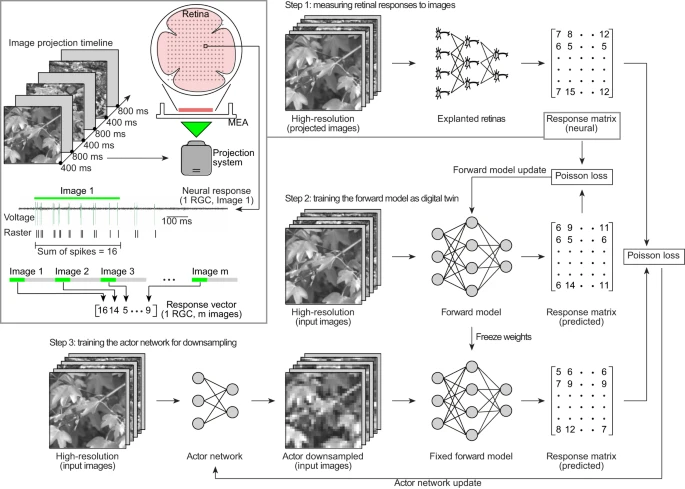

Leong F., Rahmani B., Psaltis D., Moser C., Ghezzi D., An actor-model framework for visual sensory encoding, Nature Communications 15.1 (2024). doi: 10.1038/s41467-024-45105-5. |